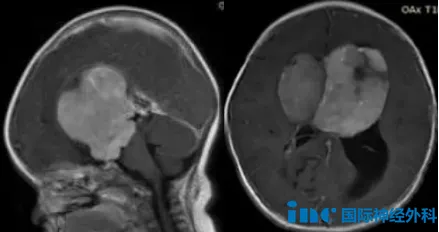

肿瘤位置太深、孩子年龄太小、脑瘤太大、手术风险很高,切除率不高不说,术后还很可能失明。小橘的母亲看着不远处熟睡的孩子,脑海中回想起医生的话,悲痛又一次席卷而来。她才刚出生...